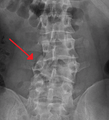

A burst fracture of L4 as seen on plane X ray

A burst fracture of L4 as seen one plane X ray